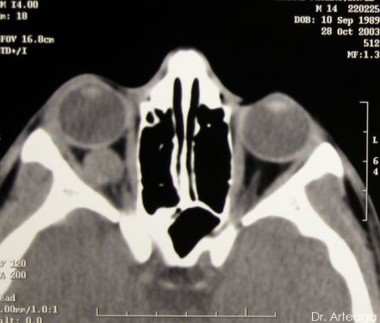

Galería de Imágenes